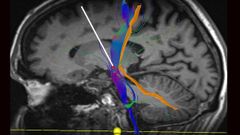

10 abr 2019 Cirugía de alta precisión para aplacar el Parkinson La unidad de Cirugía de los Trastornos del Movimiento del HUCA combina la implantación de neuroestimuladores cerebrales recargables de última generación con avanzados tratamientos farmacológicos La Voz

10 abr 2019 Asturias, pionera en la lucha contra el Parkinson La Unidad de la Cirugía de los Trastornos del Movimiento del Hospital Universitario Central de Asturias (HUCA) es pionera en España